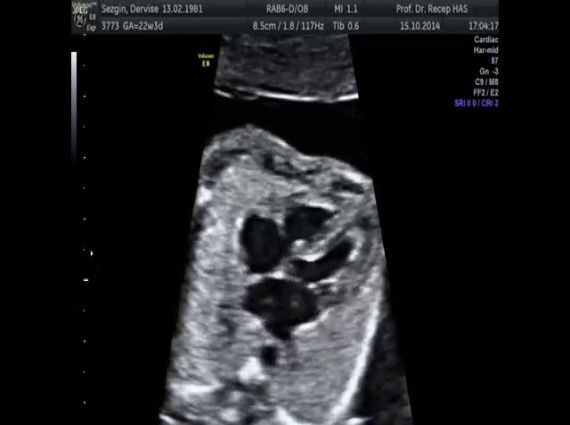

Gebelik sırasında bebeğe yapılan, normal ve anormal kalp yapılarını gösteren bir ultrasonografi yöntemidir. Ayrıca bebeğin ritim bozukluklarının teşhis ve takibinde kullanılabildiği gibi girişimsel tedavide de uygulanabilir.

Çoğunlukla gebeliğin 16-22 haftaları arasında yapılmaktadır. Özel durumlarda herhangi bir kısıtlama yoktur. Ultra ses dalgalarının bebeğe herhangi bir zararı bulunmamaktadır. En büyük avantajı, kompliksayonunun olmaması, kolay ve tekrar edilebilir olması.

Aşağıdaki hallerde fetal ekokardiyografi yapılması gereklidir;

Ebeveyninde doğuştan kalp hastalığı hikayesi bulunanlar,Kardeşlerinde doğuştan kalp hastalığı hikayesi bulunanlar,Fetal kalpte ritm bozukluğu,Annenin bazı sistemik hastalıkları, (diyabet, kollajen doku hastalığı, fenilketonuri)Bebekte kromozomal anomali şüphesi,Kalp dışı anomali bulunması, (diyafragmatik herni, hidrops, omfalosel)Bebekte polihidroamniyos, oligohidroamniyos olması,Anne tarafından bazı ilaçların alınması (lityum, amfetamin, progesteron, anti konvülsanlar).

Fetal ekokardiyografi sayesinde, bebeğin yaşamını tehdit eden, doğum sonrası hayatını etkileyen ve birkaç kez ameliyat gerektiren ağır ve karmaşık kalp ameliyatları, doğum öncesi tanınabilir ve gerekli önlemler alınabilir. Ailenin bebek ile ilgili yaklaşımında ve alınacak kararda, diğer uzmanlarla birlikte (Kadın Hastalıkları ve Doğum, Yenidoğan ve çocuk Kardiyoloji Uzmanı) ortak hareket ederek karar verilmelidir.